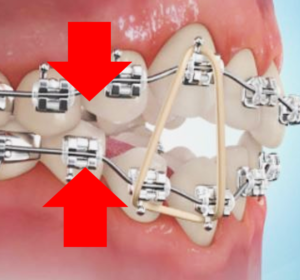

この症例の方は、咬み合わせが変化していく中で、上下顎とも奥歯が咬んでいない開咬状態になりました。

その場合、下の写真のようなMEAW(Multiloop Edgewise Arch Wire)という、ゴムかけ用のフックを付与したワイヤーを使用することがあります。

ゴムかけの力で上下の顎を咬ませることはもちろん、歯1本1本のコントロールにも優れており、歯のガタガタや捻じれが大きく通常のワイヤーだとコントロールが難しい方に有効なワイヤーです。

ただし、歯ブラシが当てにくく、物が挟まりやすいことが欠点でもあります。